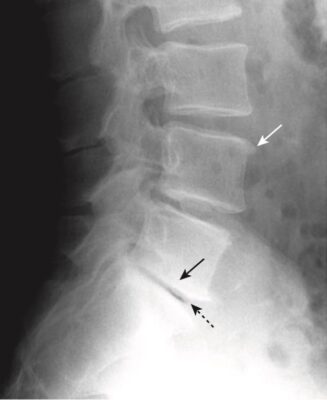

- Với tuổi tác ngày càng cao, nhân nhầy dạng gel bình thường trở nên mất nước và thoái hóa. Quá trình này dẫn đến giảm dần chiều cao của khoang đĩa đệm. Đôi khi, sự khô hoá đĩa dẫn đến giải phóng khí nitơ từ các mô xung quanh đĩa đệm, tạo nên hình ảnh đậm độ khí trong khoang đĩa đệm, gọi là hiện tượng đĩa chân không (vacuum disk phenomenon). Đĩa chân không là một dấu hiệu biểu hiện thoái hoá đĩa đệm giai đoạn muộn (Hình 7).

- Có sự thu hẹp khoang đĩa đệm (hẹp khe “khớp”). Bản thân các thân đốt sống cũng có những thay đổi.

- Các mặt thân đốt (bản tận) của các thân đốt sống tiếp giáp với nhau bị xơ cứng (đặc xương). Có các gai xương nhỏ ở rìa của các thân đốt sống tại mỗi khoang đĩa đệm (xem Hình 7).

- Đồng thời, thường có sự thoái hóa của vòng xơ bên ngoài, tạo nên các gai xương lớn hơn ở các bản tận so với các gai xương do thoái hoá nhân đệm.

- Cần lưu ý rằng các gai xương là một dấu hiệu rất thường gặp, tỷ lệ tăng khi tuổi càng tăng, và phần lớn những người có gai xương ở cột sống là không có triệu chứng.